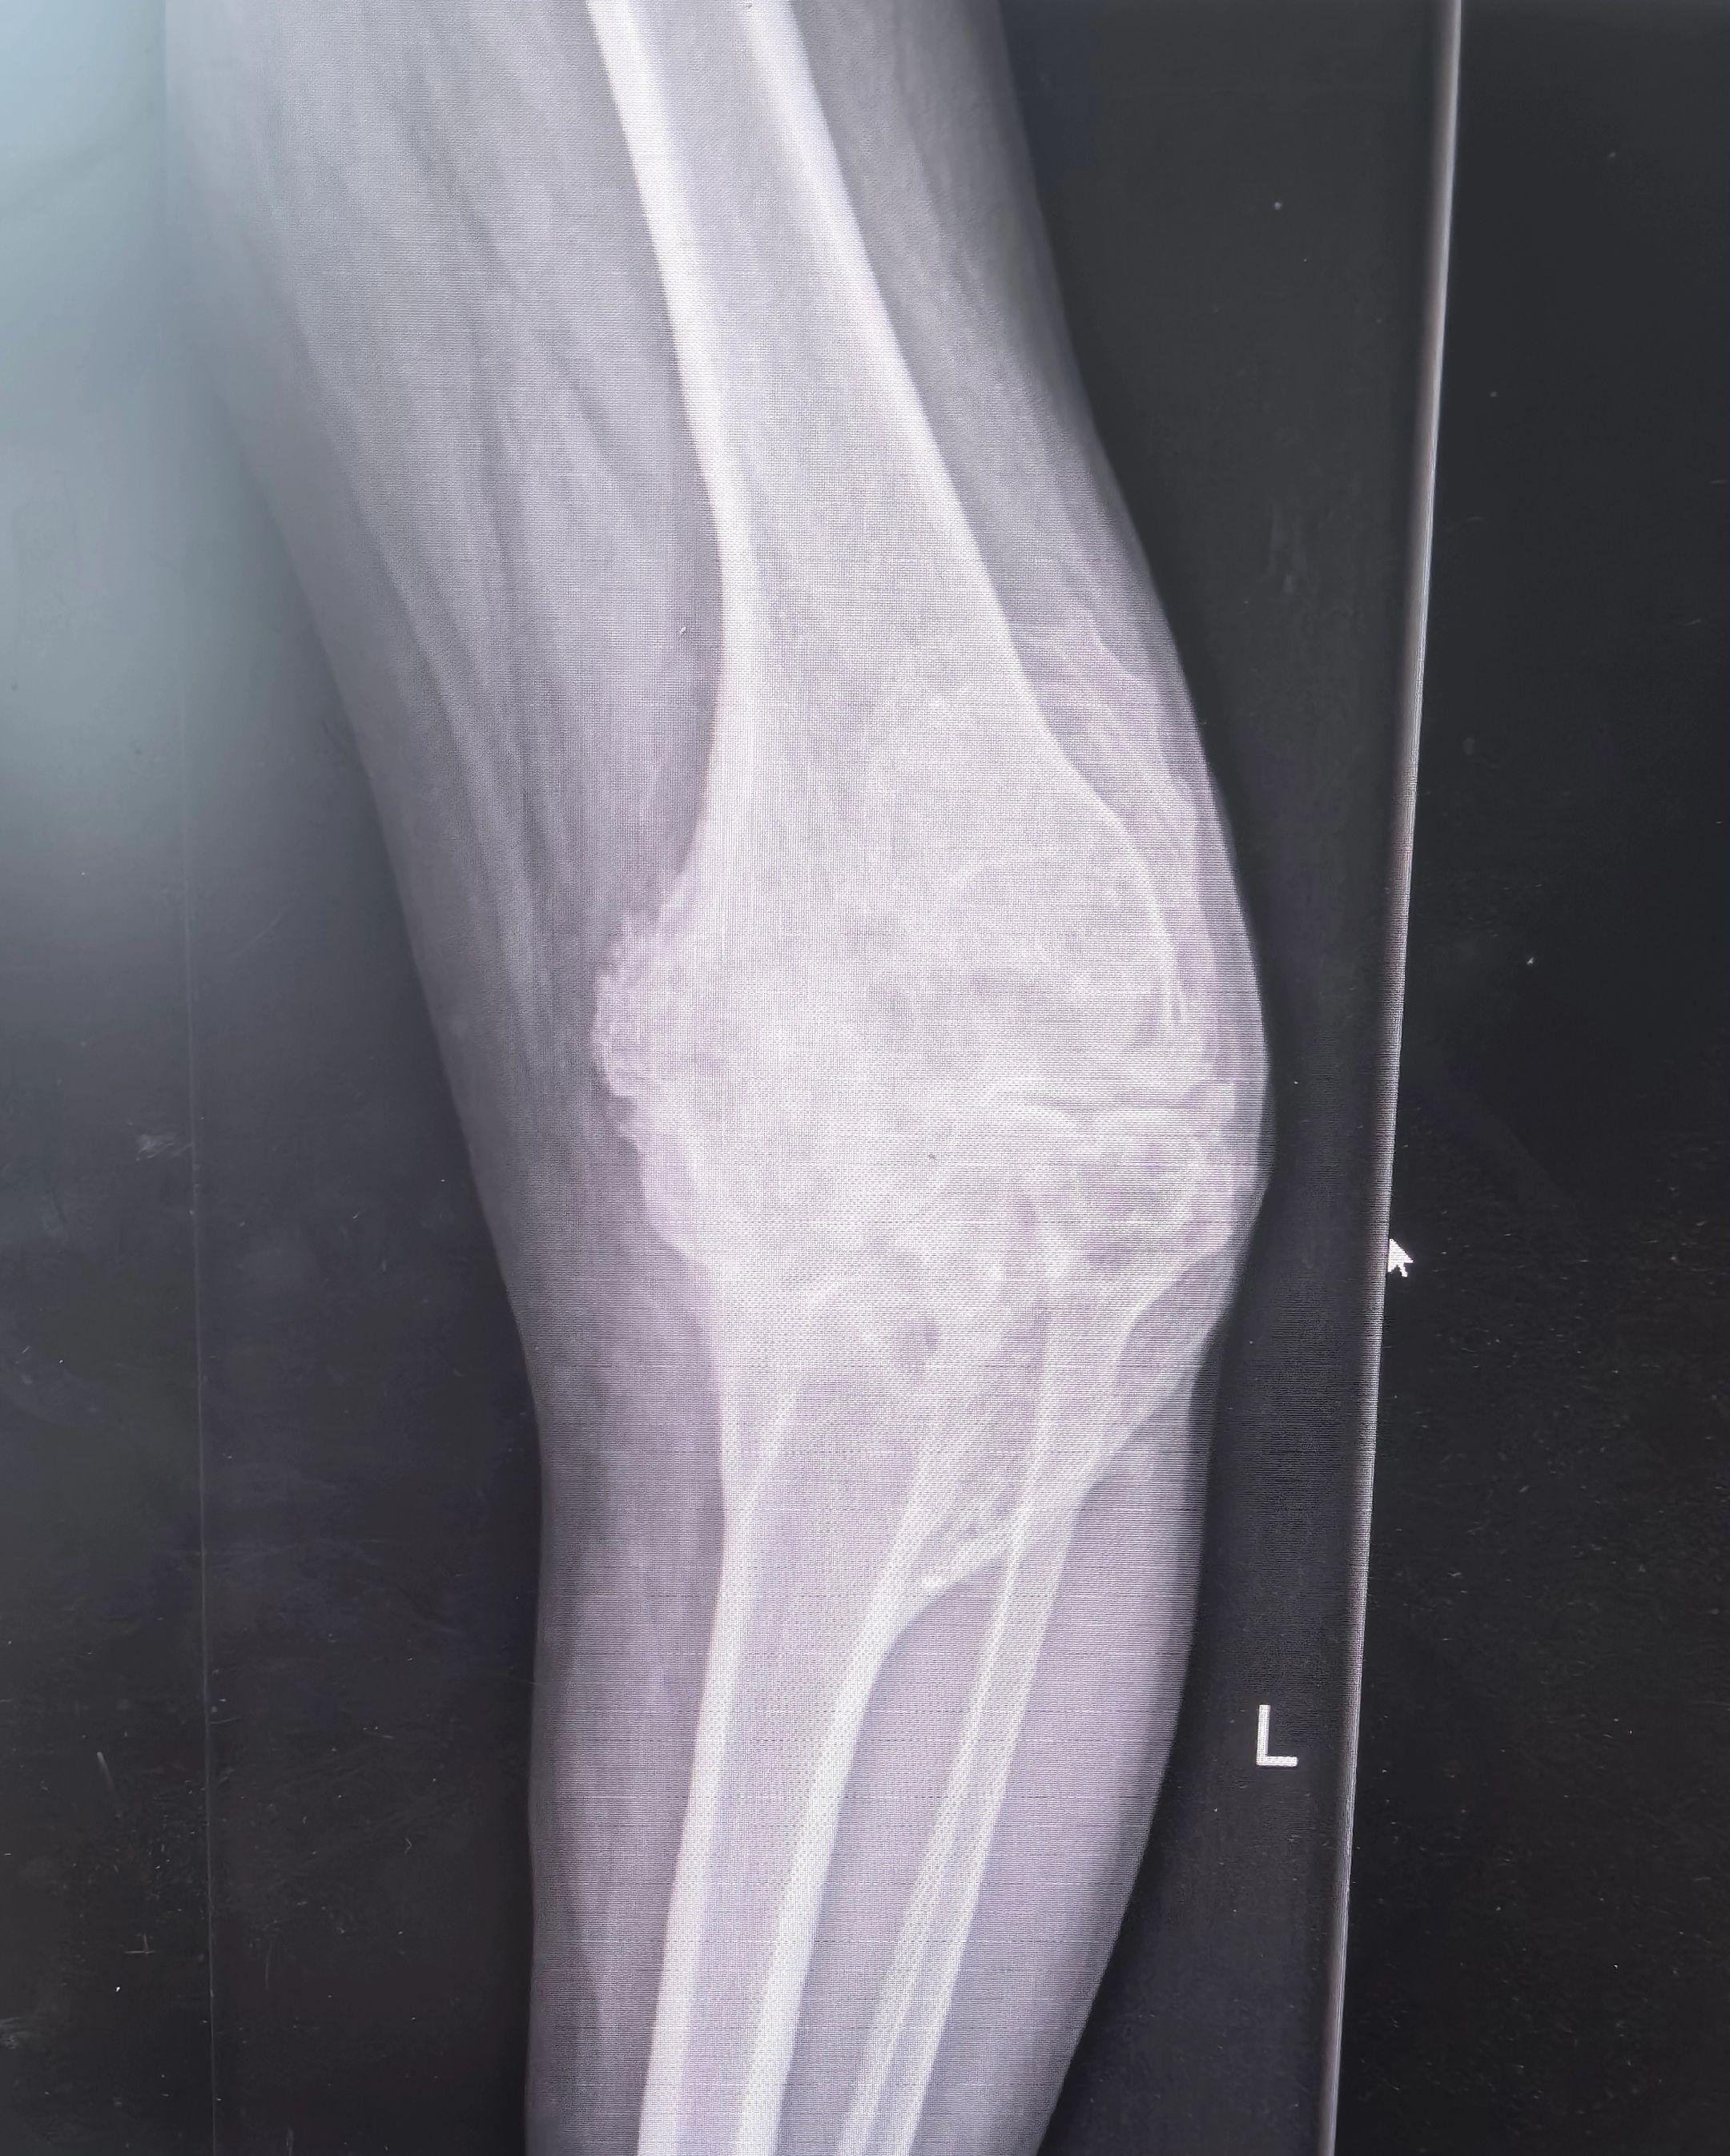

创伤性关节炎,膝关节置换。19岁胫骨平台骨折畸形愈合,未处理,现52岁,重度创伤性膝关节炎,疼痛,无活动度,行走困难。各位老登,怎么破?铰链膝?CCK?定制膝?